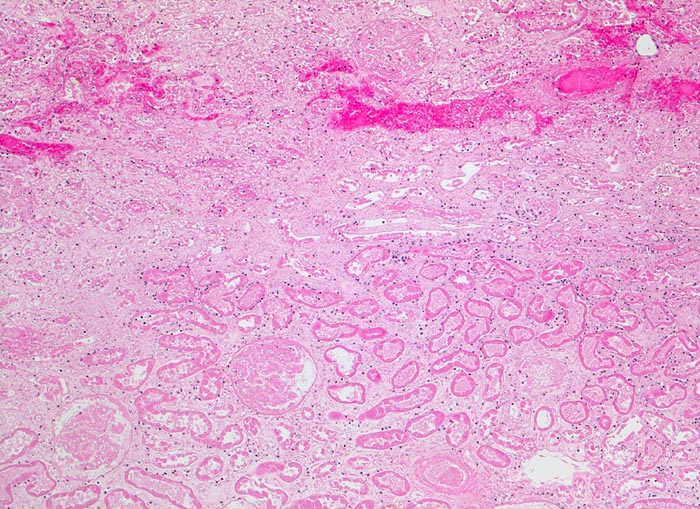

akuter Niereninfarkt mit hämorrhagischem Randsaum

Ausschnitt aus dem Randbereich der Koagulationsnekrose mit hämorrhagischem Randsaum (oben)

Chronisches Vorhofflimmern mit Morbus embolicus: anämische Infarkte verschiedenen Alters in beiden Nieren und in der Milz. Alte abgebaute Enzephalomalazie im Versorgungsbereich der Arteria cerebri media rechts.

Histologie

50